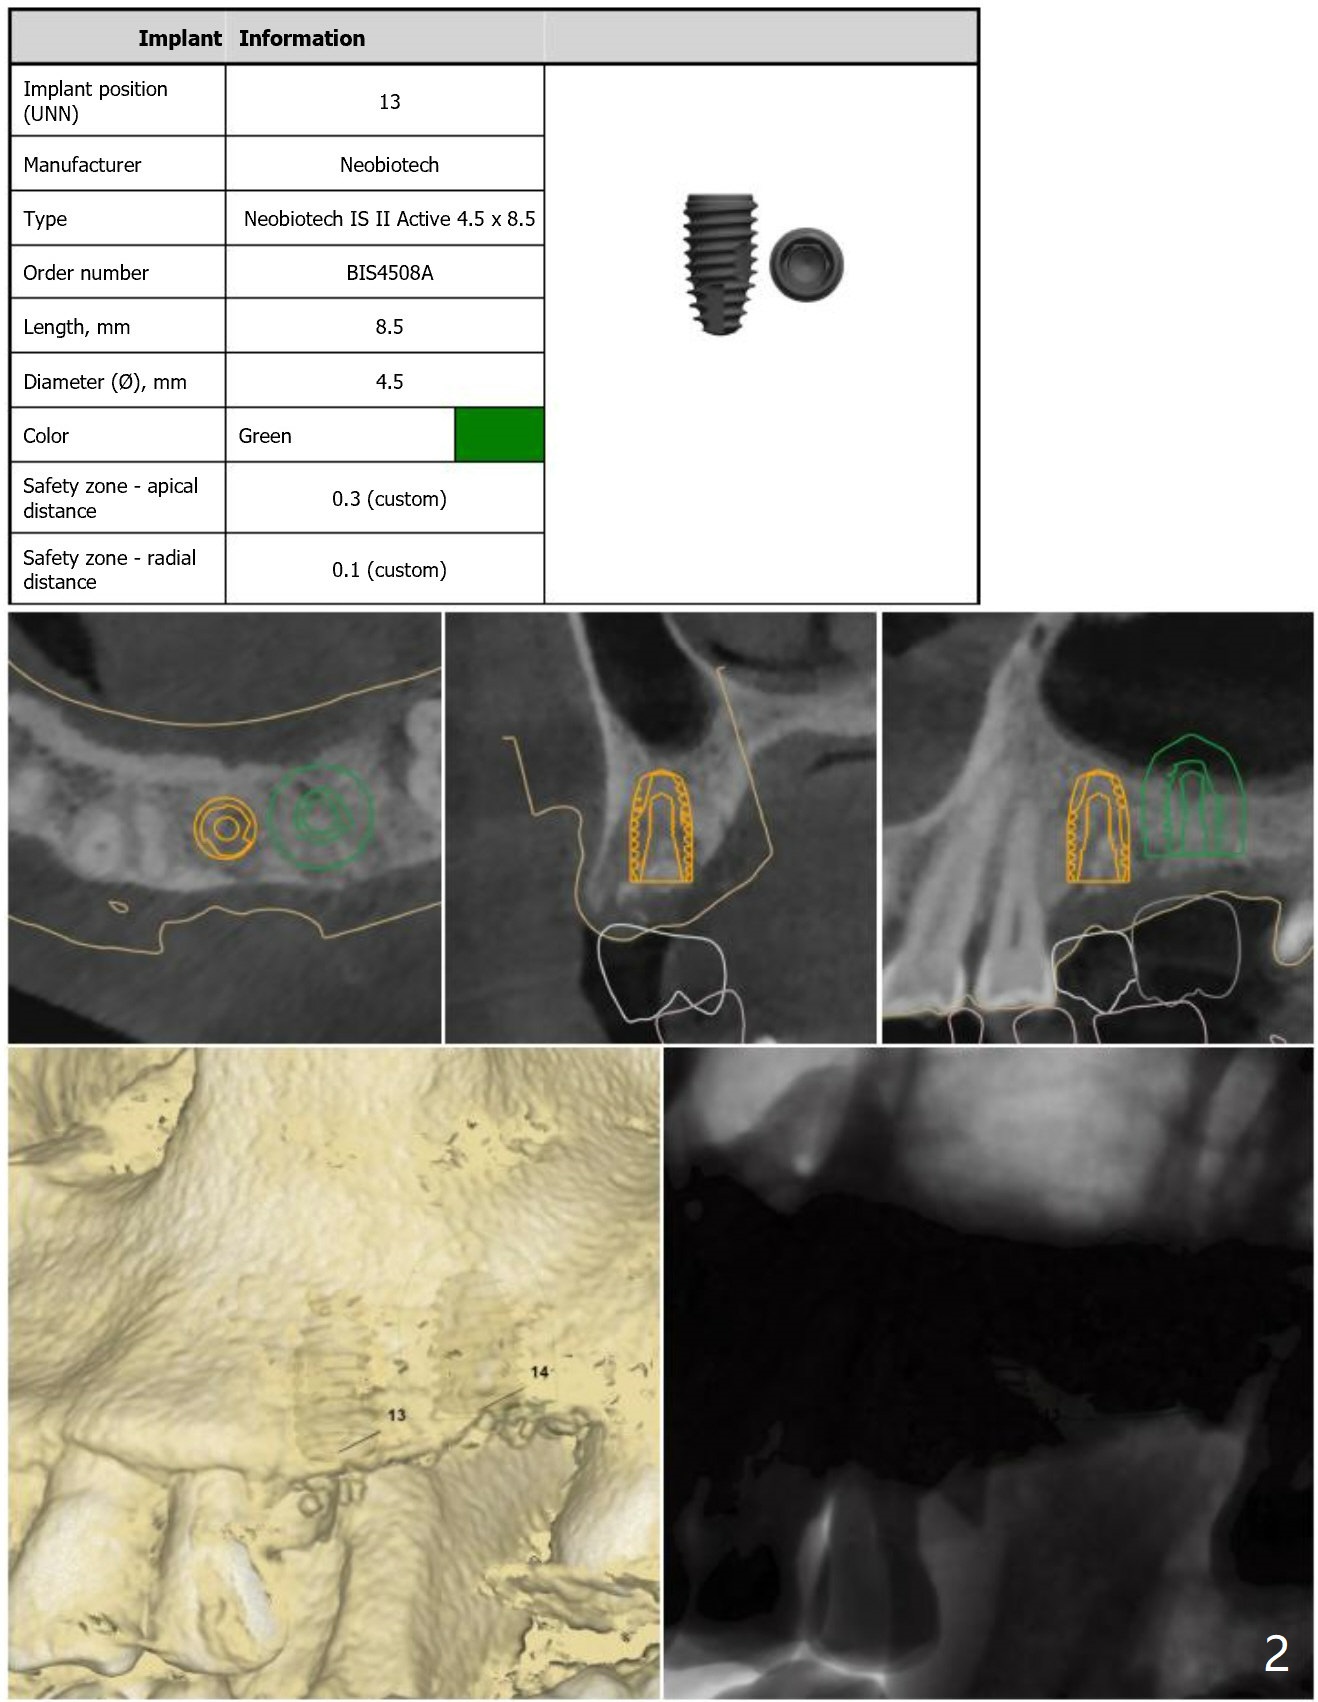

Short Implants with Sinus Lift at #14

Return to Upper Molar Immediate Implant, Armaments

Xin Wei, DDS, PhD, MS 1st edition 08/14/2018, last revision 08/30/2018